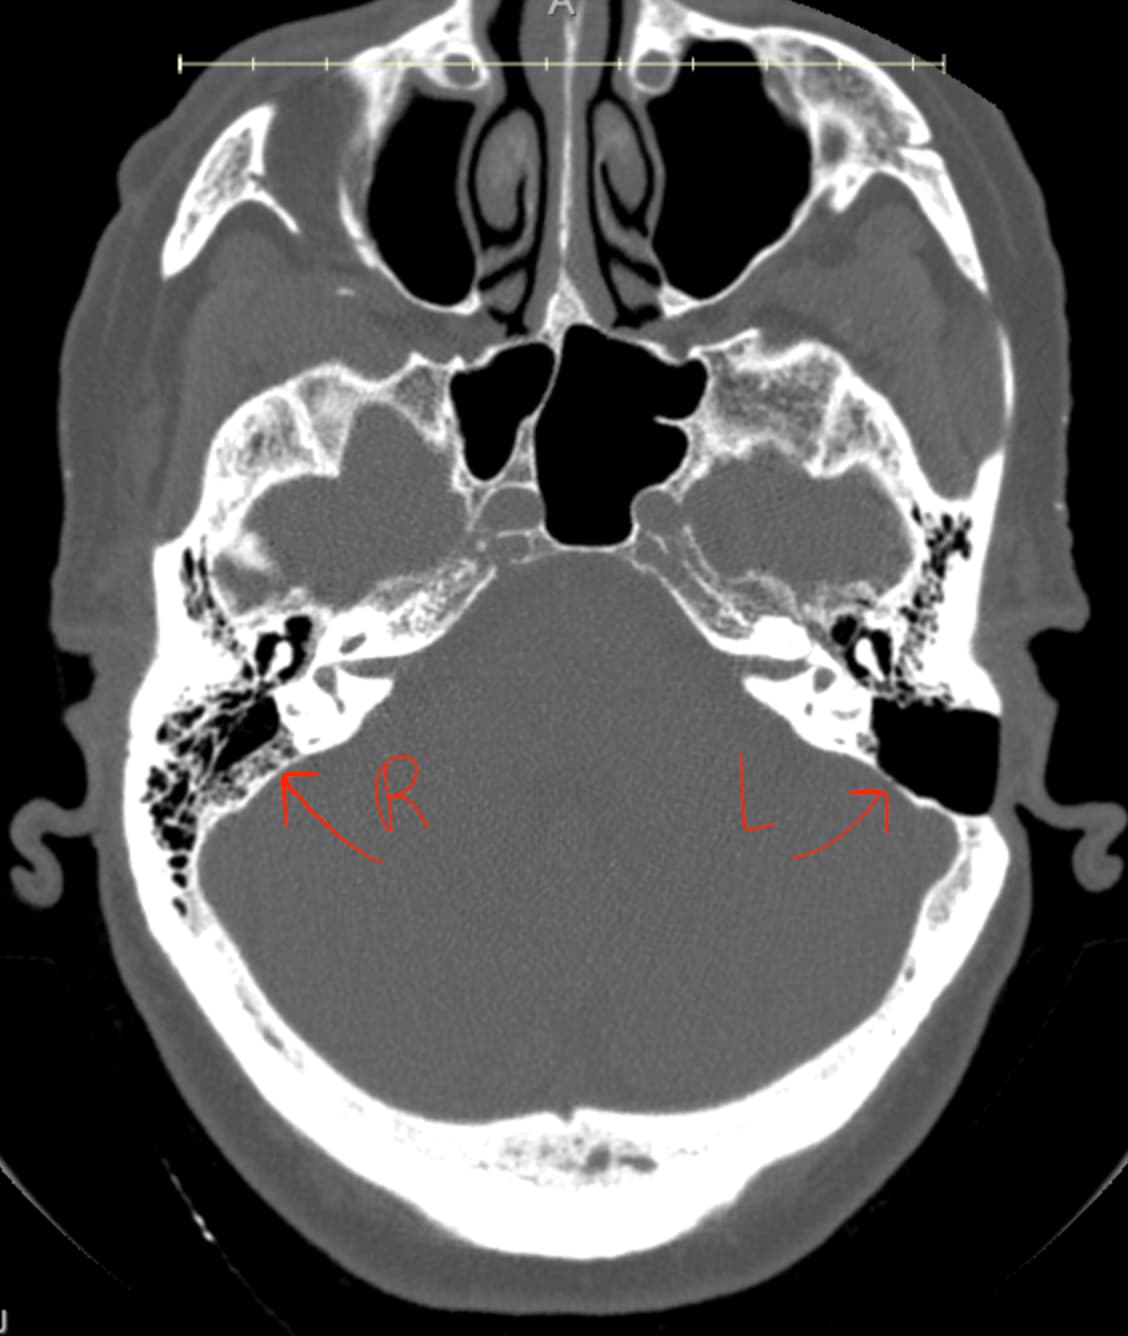

Here’s what the CT scan Dr. Hepworth had me get reported:

Left temporal bone: The external auditory canal is normal. There is a left wall of mastoidectomy. There is a small metal region in the medial mastoid resection bed. The bone over the left sigmoid sinus is thin and may be dehiscent. The bone over the medial and superior margin of the mastoid resection bed is thin and may be dehiscent. There is no mastoid fluid or demineralization. There is no middle ear fluid. The bone over the jugular bulb is thin at the level of the middle ear cavity.

You can see the difference between right & left inner ears in this CT image:

Sorry your symptoms didn’t improve with IJV surgery. I can clearly see the difference on the image you posted. What was the reason for your inner ear surgery? I also have a sigmoid plate dehiscence, but none of the ENTs I’ve seen say much about it. They really only talk about the SSCD.